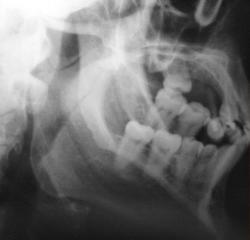

А это визави.

У этого 3 г. назад нелеченная травма, теперь остеомиелит

на мой взгляд здесь перелом суставного отростка